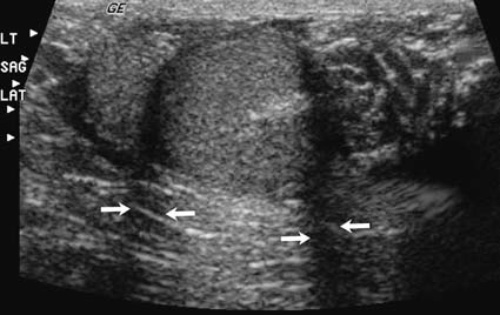

Значительная часть ультразвуковых волн происходит из центра луча. Примерно 1% энергии ультразвука распределяется от периферии – эти части потока являются боковыми долями, которые в обычных условиях слабы для формирования значимого эха. Однако бывают случаи, когда эти волны (боковые доли) сталкиваются с сильными отражателями и образуют артефакты. Нужно отметить, что такие артефакты образуются из-за того, что программный алгоритм интерпретирует образованные эхо как образованные из центрального потока, например, ложное наличие эхогенной желчи в желчном пузыре (рисунок 8).

Рисунок 8. УЗИ желчного пузыря: боковые доли. А – желчный пузырь (пациент находится в положении лежа на спине), стрелками указаны множественные эха, что дает основание полагать наличие отложений или мелких камней. В – УЗИ того же пациента в положении лежа на боку демонстрирует, что эхо, полученное на снимке А, является артефактом, а просвет желчного пузыря чистый